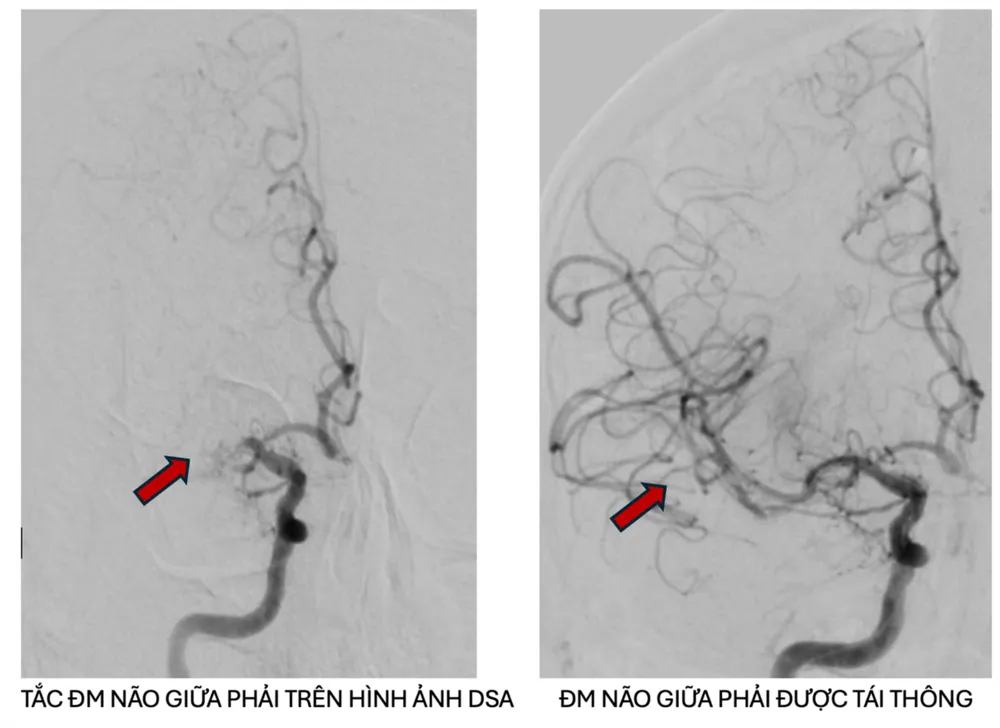

Kết quả chụp MRI tưới máu não kết hợp với phần mềm trí tuệ nhân tạo RAPID AI để đánh giá vùng mô não bị tổn thương cho thấy bệnh nhân bị tắc động mạch não giữa phải trên nền hẹp nặng do xơ vữa động mạch, có chỉ định can thiệp mạch não lấy huyết khối. Người bệnh được chuyển đến Đơn vị can thiệp mạch máu thần kinh tiến hành lấy huyết khối và nong vị trí hẹp mạch máu, kết quả động mạch được tái thông tốt sau can thiệp.

Sau 1 ngày can thiệp, người bệnh tỉnh táo, tiếp xúc tốt, sinh hiệu ổn định, sức cơ nửa người bên trái cải thiện khá, chụp MRI kiểm tra ghi nhận tái thông mạch máu tốt, tự đi lại được, ăn uống bình thường. Đến sáng 2-6, người bệnh tự đi lại gần như bình thường, chức năng nói cải thiện tốt, ăn uống tốt, sinh hiệu ổn định và tiếp tục được chăm sóc, phục hồi chức năng, dự kiến sẽ sớm trở về nước.